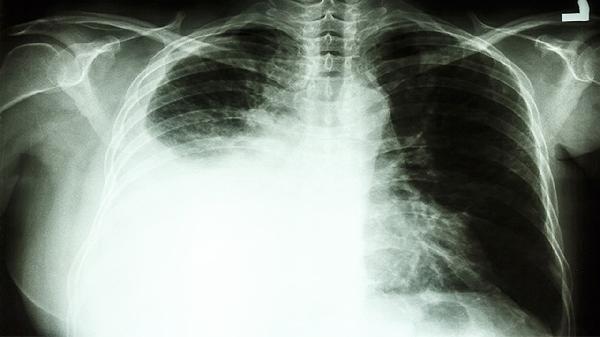

紫龙金片是中成药,主要成分包括黄芪、当归、白英等,具有益气养血、清热解毒的功效。在肺癌治疗中,该药常作为辅助用药,与放疗、化疗等联合使用。部分患者用药后可能出现乏力减轻、食欲改善等效果,但无法替代手术或放化疗等主要治疗手段。用药期间需定期复查肿瘤标志物及影像学检查,评估病情变化。